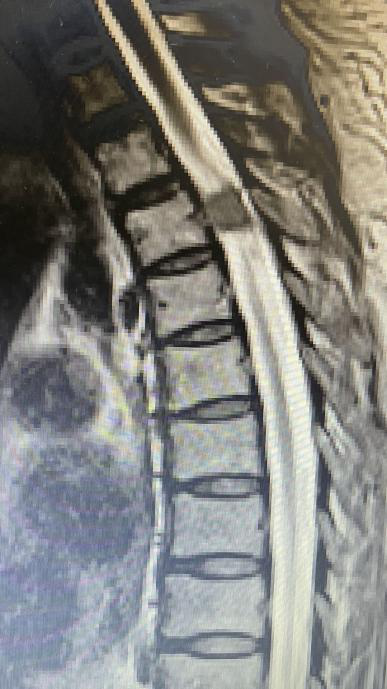

接诊的骨科主任医师徐杰让王奶奶做了检查,发现导致王奶奶双腿麻木的元凶,竟然是因为她的胸椎管内悄悄地长了一个脊膜瘤。

这个肿瘤必须手术切除,可小小的椎管内长了肿瘤,要在手术中准确找到它的位置,显然不是件容易的事。倘若稍有不慎,还可能损伤脊髓,延长术后恢复时间。

敲定了手术方式,手术如期进行。在徐杰的引导下,“天玑”灵活地挥动着机械臂,紧贴肿瘤边缘,磨出一个近似长方体的区域,很快就将肿瘤位置锁定。随后,徐杰娴熟地运用他自创的手术方式切除了整个肿瘤,术后影像显示肿瘤切除范围与术前规划几乎完全一致。

来看看手术是如何操作的

手术时,医生将病人的三维CT图像导入机器人图像系统,主刀医生在机器人系统的计算机上,用鼠标规划好在脊椎椎板上开窗的最小边界和最佳斜率方向,路径边界避开了重要的结构并保留脊柱关节突;随后,启动机器人的机械臂,自动精确走位到该边界,利用携带的磨钻直接在脊椎上开一小窗。然后,医生在显微镜下用显微外科技术打开脊髓神经的硬膜,完整切除肿瘤,该肿瘤为钙化性脊膜瘤。